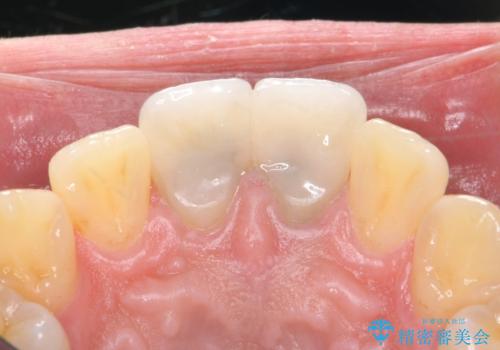

歯のガタつきも解消することができました。

e-maxクラウンでは仮着ができませんが、今回は一回でご満足いただける修復ができました。